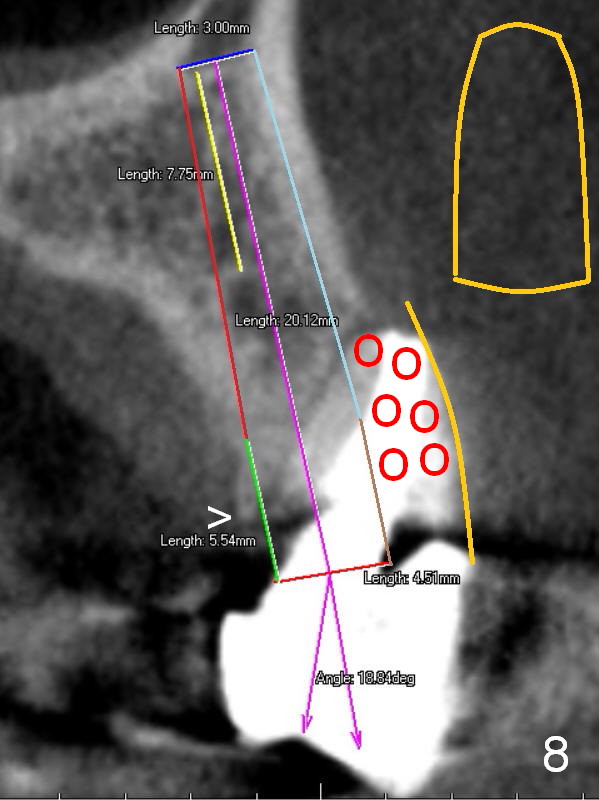

A 4.5x14 mm bone-level or 4.5x17 mm tissue-level implant appears to be appropriate for the site according to the PA (Fig.6,7).  CBCT shows that there is enough bone to place a 4.5x20 mm tissue-level implant (Fig.8).  This is more appropriate, considering the large radiolucency (Fig.5), the age of the patient (possibly osteoporosis), and the maxilla (bone softer than that of the mandible).  The implant will be supported by approximately 8 mm solid bone apically (Fig.8).

After extraction, the bottom of the socket must be oblique (Fig.9 arrowheads). As usual, osteotomy is initially at the junction of palatal (Fig.10 P) 1/3 and middle 1/3 perpendicular to the plate.  Once the drill gets engaged, the trajectory is to be changed (Fig.11 curved arrow) so that the apical end of the osteotomy (red line) is as close to the buccal plate (B) as possible.  The purpose is to keep the palatal end of the osteotomy as palatal as possible.  In spite of the effort, an angled abutment is expected, as large as 20 degree (Fig.8 purple angle).

After preparation of the implant and abutment and fabrication of an immediate provisional, a cone-shaped Osteo-tape (Fig.8 orange outline) is inserted against the buccal socket wall (most likely completely soft tissue), followed by bone graft (red circles, to the level of the palatal crest (>)).